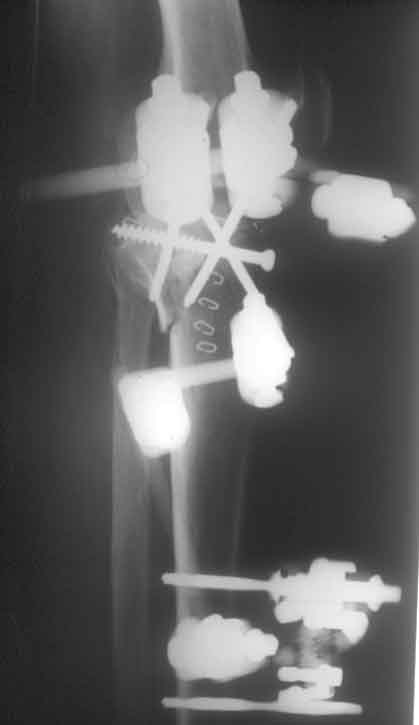

Tibiakopffraktur mit tiefer Impression (Schichtaufnahme) Anheben der Fraktur, Unterfütterung mit allogenem Knochen, minimalinvasive Stabilisierung mit Spongiosaschrauben, neutralisieren der Fraktur mit Hoffmann II Fixateur (freie Pinplazierung)

Hoffmann II Montage mit freier Pinplazierung proximal. Wenige Tage nach der Operation besteht freie Beweglichkeit im Kniegelenk Befund 8 Wochen nach der Operation, der Fixateur kann entfernt werden.